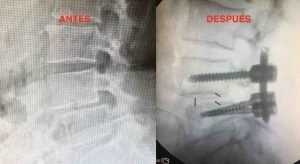

Tras el fallo del tratamiento conservador y tras valorar radiografías dinámicas de columna lumbar en flexión extensión, se recomienda a la paciente artrodesis circunferencial percutánea L4-L5.

Radiografía previa a la cirugía y control intraoperatorio